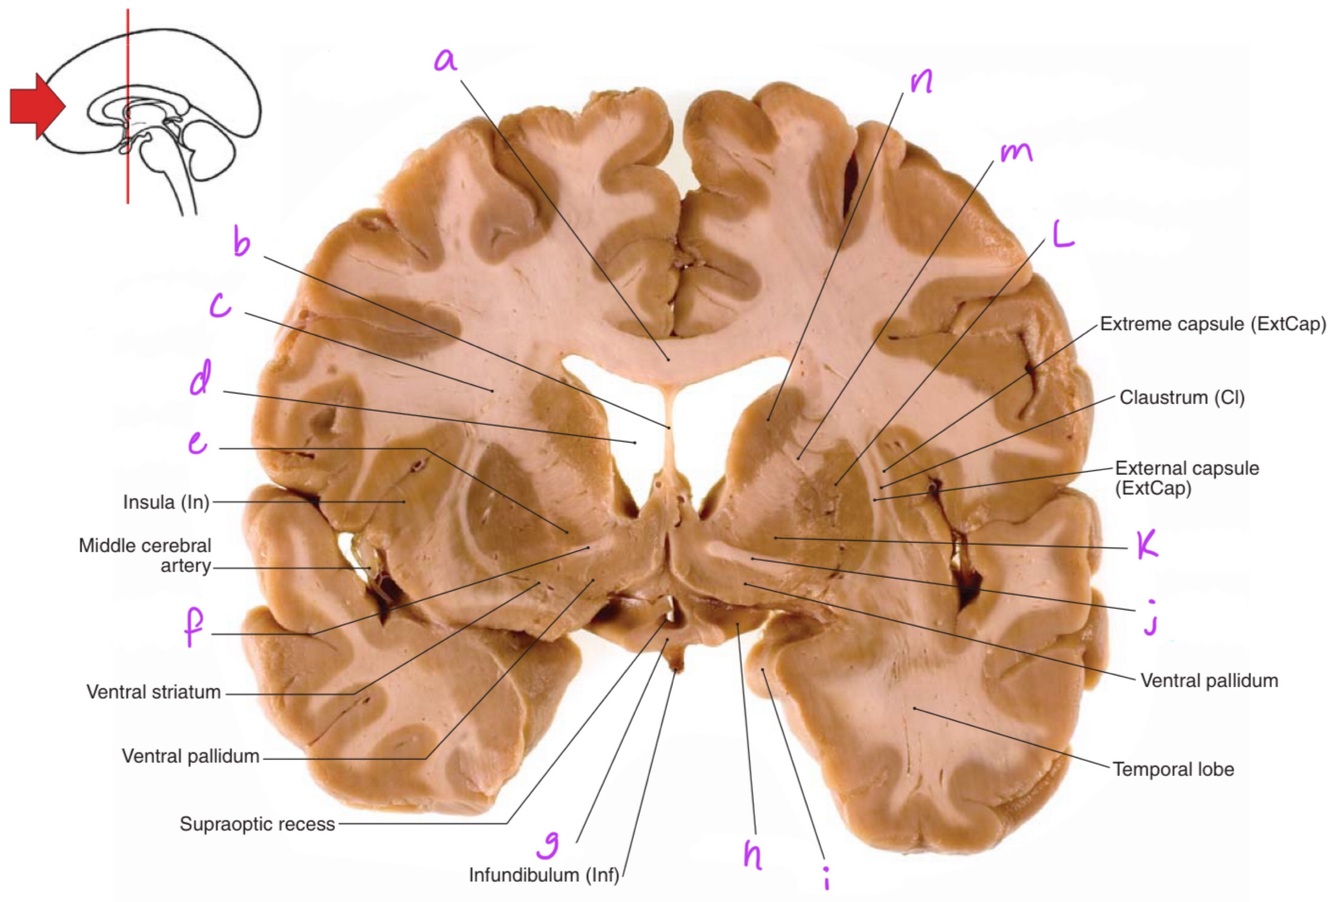

a

Body of corpus callosum

b

septum pellucidum

Q

Corona radiata

Anterior horn of lateral ventricle

Globus pallidus

Anterior commissure

Optic chiasm

Optic tract

Uncus

Putamen

Anterior limb of internal capsule

Head of caudate nucleus